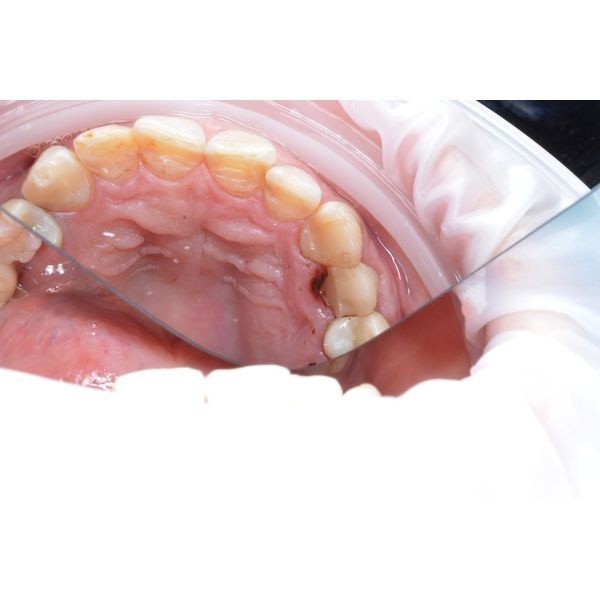

При осмотре полости рта виден зуб верхней правой челюсти, у которого щёчная стенка сохранена, а нёбная — нет. Десна со стороны нёба изменила цвет, при пальпации (прощупывании) и зондировании (проверке с помощью тонкого инструмента — зонда) возникает боль. Глубина дефекта — 5 мм.

По результатам компьютерной томографии:

- выявлен глубокий скол коронковой (видимой) части зуба и корня;

- корневые каналы запломбированы до верхушки;

- признаков воспаления вокруг корня нет.